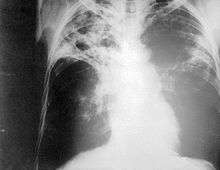

Chest photofluorography, or abreugraphy (also called mass miniature radiography), is a photofluorography technique for mass screening for tuberculosis using a miniature (50 to 100 mm) photograph of the screen of an X-ray fluoroscopy of the thorax, first developed in 1936.